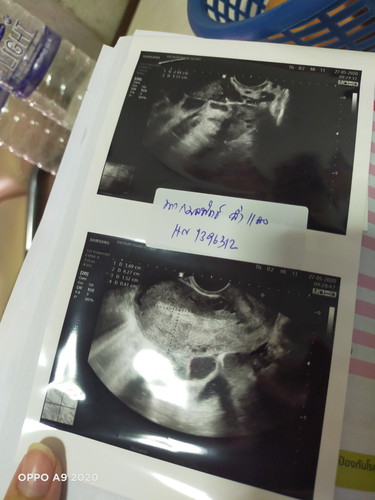

ตอนนี้ตั้งครรภ์ได้8สัปดาห์ค่ะ มีเลือดออกช่องคลอด มีก้อนเลือด ไปให้หมอซาวด์แล้วไม่เจอเด็ก ทั้งซาวด์ช่องคลอดก็ไม่เจอเด็กค่ะ หมอเลยขอเจาะเลือด ผลเลือดก็ขึ้นว่าตั้งครรภ์อยู่ พรุ่งนี้หมอนัดเจาะเลือดอีกค่ะ? มีใครเคยเป็นแบบเราไหม

เราเป้นค่ะท้องได้9วีคไปซาวไม่เจอเด้กซาวหน้าท้องและช่องคลอดก้ไม่เจอเราเลยไปคลีนิกเพื่อความแน่ใจหมอตรวจและอัลตร้าซาวอีกรอบสรุปหมอบอกว่าท้องลมและก้มีเลือดออกสีน้ำตาลกลิ่นคล้ายเป้น ป.จ.ด

เคยค่ะเมื่อปีที่แล้ว ปวดท้องมากไปหาหมอ ซาวทางช่องคลอด ไม่เจอเด็ก หมอบอกท้องนอกมดลูก แต่ถ้าเลือดไม่ออก ไม่ปวดท้อง แสดงว่าเด็กอาจจะตัวเล็กมองไม่เห็น

ภาวะท้องลมจ้า ตรวจฉี่ขึ้นสองขีดแต่พอซาวแล้วเหนแต่ก้อน ถ้าก้อนเลือดไม่หลุดออกมา ต้องไปขูดมดลูกเคยเปนตอน ปี61